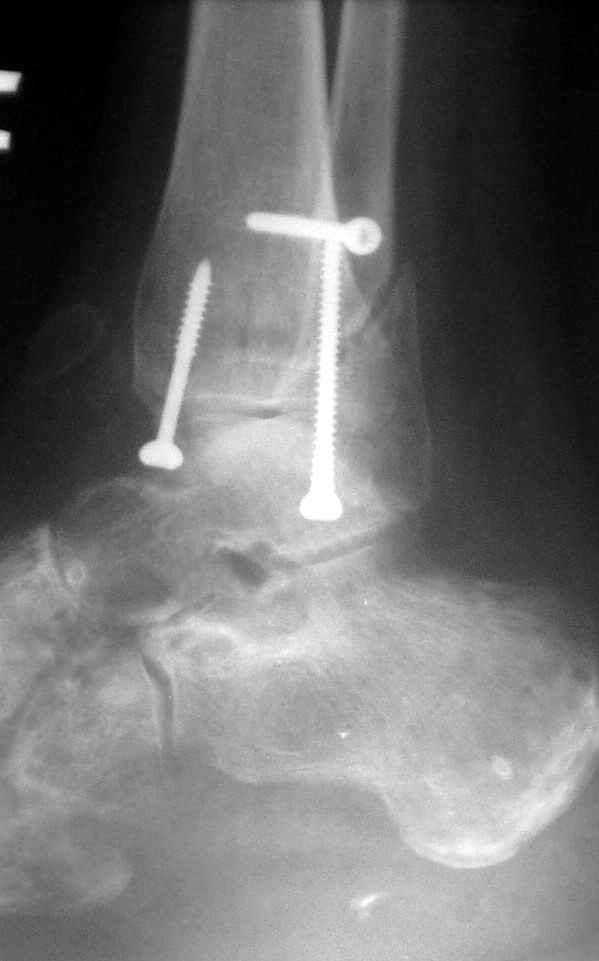

Ниже рентгенограммы

До операции 28 июля

Операция 29 июля

Через месяц

Боковой через месяц

15 ноября прямой

15 ноября боковой

15 ноября трехчетвертной

12 января прямой

12 января боковой

12 января трехчетвертной

Риторический вопрос - в каком руководстве рекомендован такой способ остеосинтеза наружной лодыжки?

Очевидно, такой результат операции был запрограммирован. При невосстановленной длине и практически нефиксированной малоберцовой кости (этот кортикальный винт - как карандаш в стакане), при неустраненном подвывихе, невправленной и тоже нефиксированной внутренней лодыжке нет стабильной вилки сустава. Если такую операцию сделать даже сразу, а не через 4 месяца, то результат ожидаем

тот же.